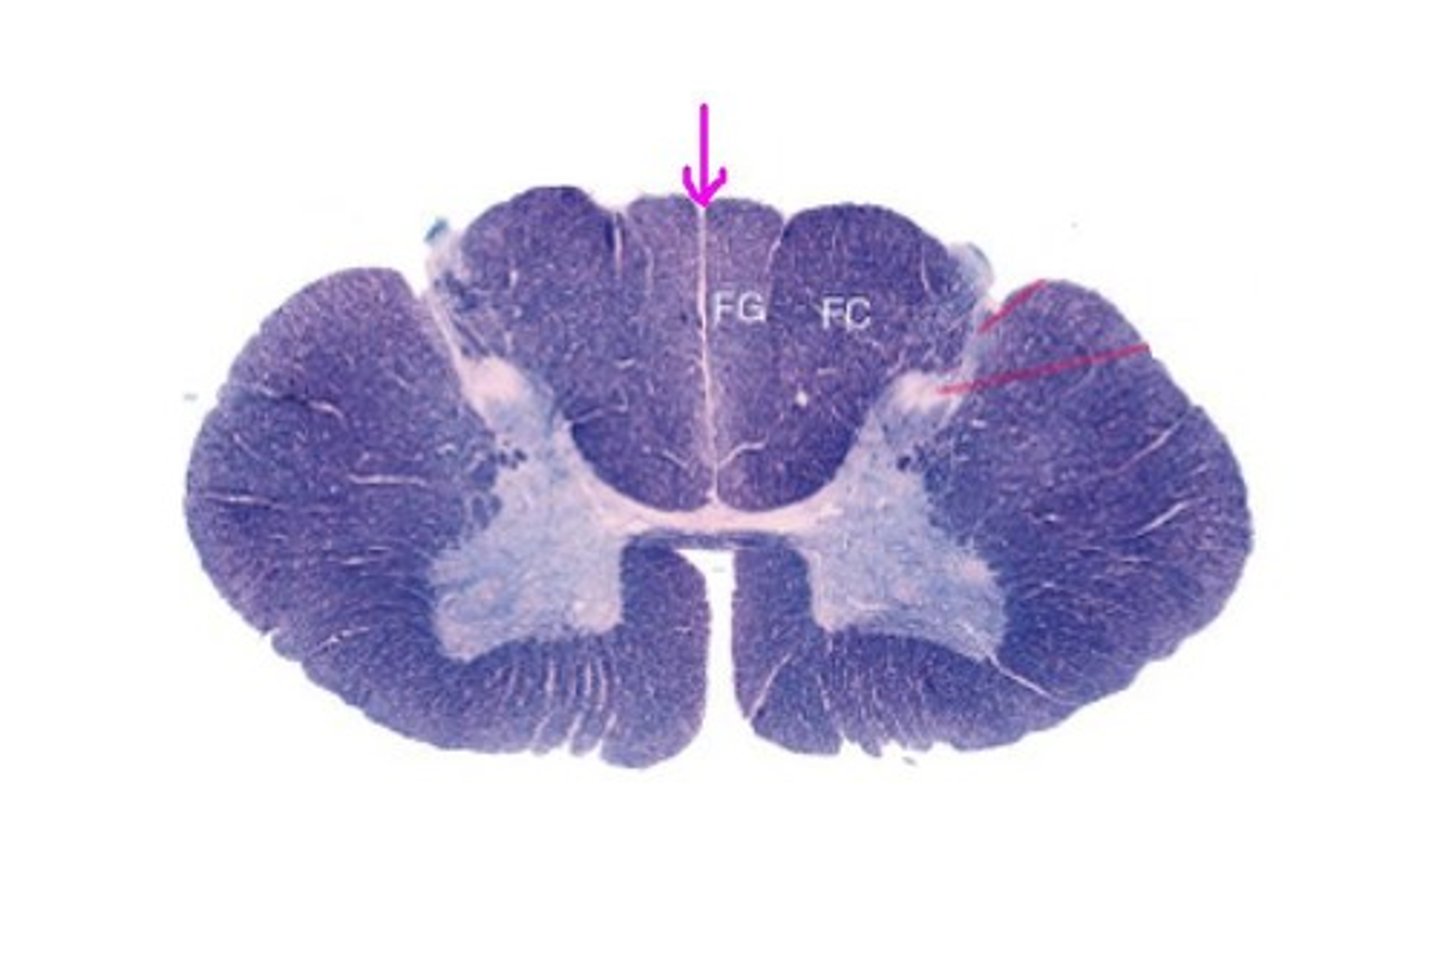

Posterior median sulcus

Anterior Median Fissure

A

B

anterior funiculus

anterior horn

D

Central Canal

E

posterior horn

f

lateral horn

g

posterior funiculus

lateral funiculus